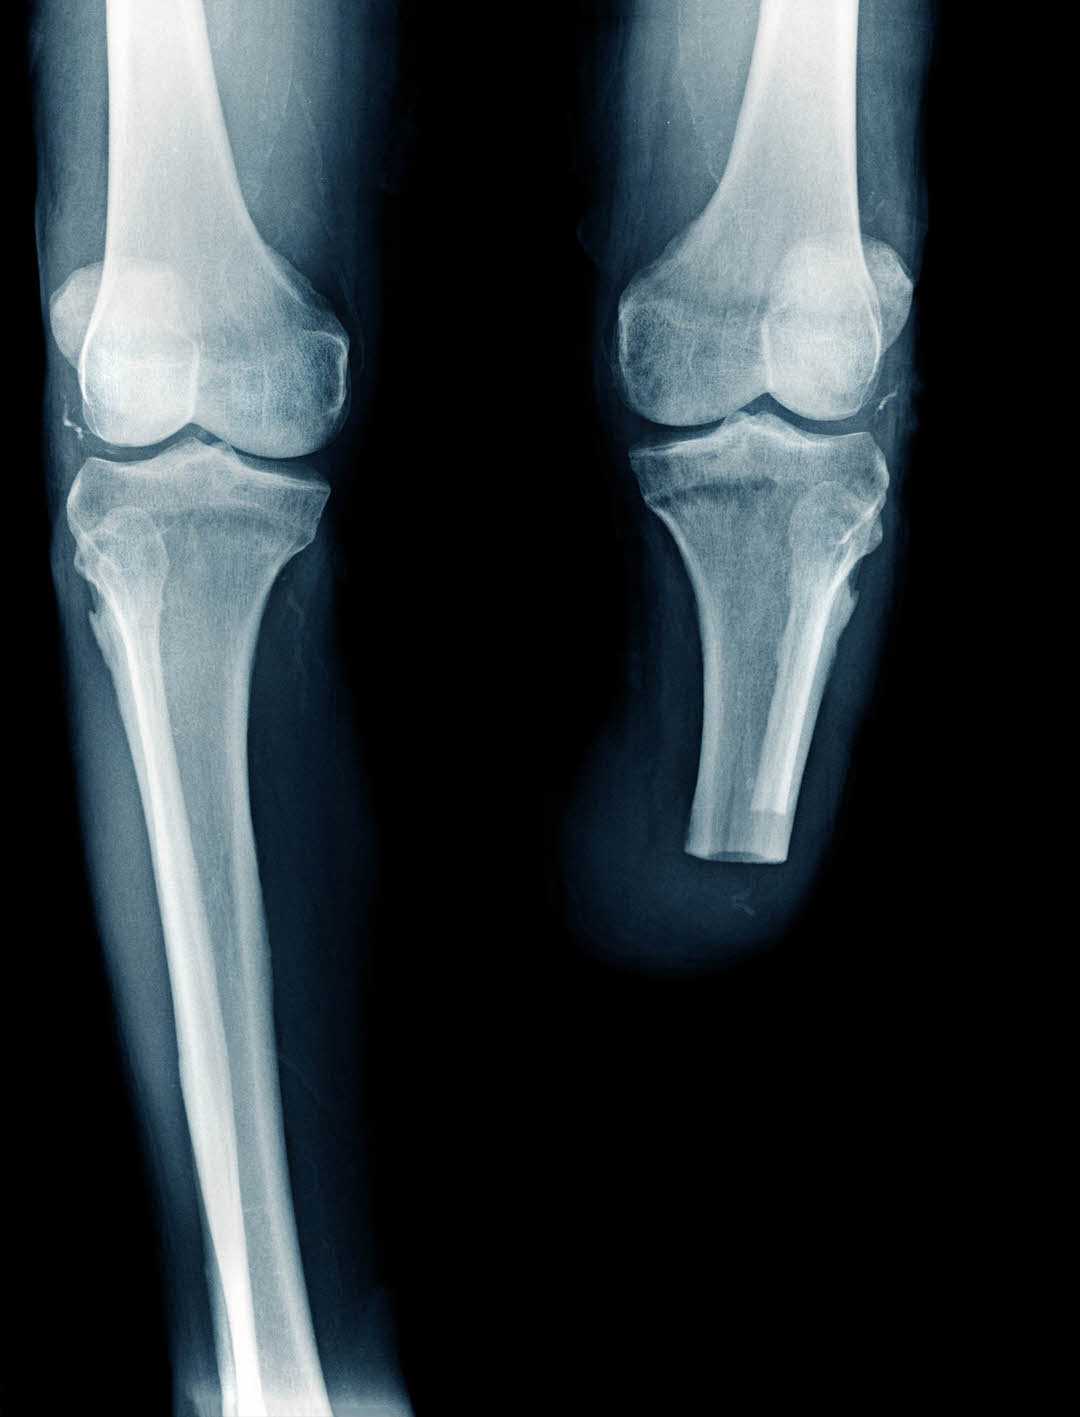

An amputation of a limb may be the ultimate result of a medical malpractice claim. This may result from a surgical error, an erroneous diagnosis, or failure to timely diagnose and treat a condition or injury, and even a medication error. If you believe that an amputation was the result of medical malpractice, you should contact an experienced medical malpractice attorney as soon as possible.

Amputations have an obvious impact on the amputee. This is often a life-altering event, both physically and psychologically. Although technology in prostheses has come a long way, to allow maximal functioning, there are certain circumstances where function remains limited. There can also be permanent and severe phantom pain in the missing limb.

Failure to amputate a sufficient portion of a limb may itself be malpractice in certain circumstances. For example, a diabetic patient with a gangrenous toe may require more than the toe to be removed to prevent further spread, illness, and even death. The failure to remove a sufficient portion of the limb in the first instance could result in multiple surgeries to the same limb, with each taking progressively more off and the patient getting sicker and closer to death each time not enough is removed.